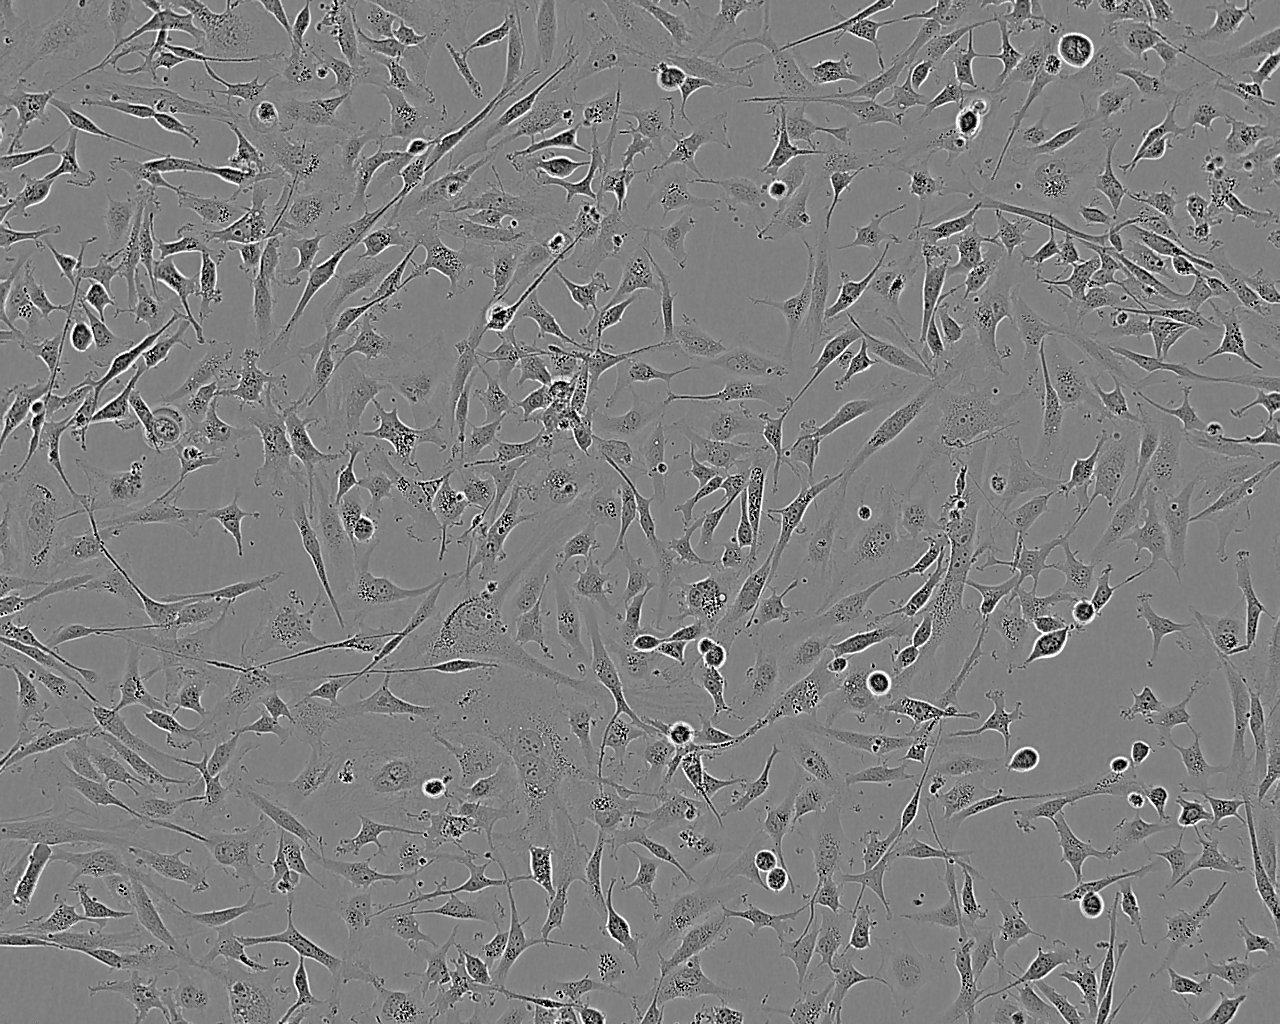

Images